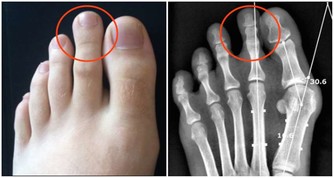

口腔潰瘍的情況下密切接吻有可能感染艾滋病。

至於很多人擔心,有口腔潰瘍的情況下接吻感染,就​​算真的發生,也是因為血液暴露,歸於血液傳播,而不能說接吻是艾滋病的一個傳播途徑。